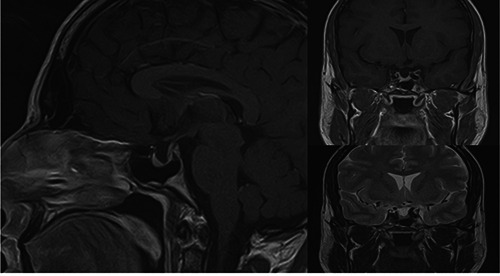

石化耳是一种罕见的临床实体,其特征是正常的柔性耳廓软骨进行性硬化,导致部分或完全耳廓僵硬。在许多情况下,它提供了有价值的临床线索,使临床医生能够在未得到诊断的患者中发现内分泌病变(特别是Addison病)。我们提出了第一个记录的石化耳病例,导致继发性肾上腺素减退和生长激素缺乏症(GHD)的诊断。此外,我们回顾了相关文献。石化耳综合征可能是其他全身性疾病的一种被低估的临床表现。有时,即使在没有典型特征的情况下,它也可以作为怀疑潜在内分泌疾病的有用而简单的临床线索。

Petrified ear is a rare clinical entity characterized by the progressive hardening of normal, flexible auricular cartilage, leading to partial or complete auricular stiffness. In many cases, it provides a valuable clinical clue that allows the clinician to detect endocrinopathies (particularly Addison's disease) in a patient who has not received a diagnosis. We present the first documented case of petrified ears, which resulted in the diagnosis of both secondary hypoadrenalism and growth hormone deficiency (GHD). Additionally, we review the relevant literature. Petrified ear syndrome is probably an underreported clinical manifestation of other systemic disorders. It may, at times, serve as a valuable and simple clinical clue to suspect underlying endocrinopathies even in the absence of typical features.